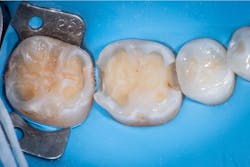

Caries lesions were removed and air abrasion was employed to remove impurities on the unprepared tooth surfaces and create increased surface area for bonding. Preparation of the class II carious lesions revealed demineralization on the adjacent tooth structure (figure 3). When lesions such as these are discovered, dentists are often at a crossroads whether to intervene or monitor the area for progression. It is my experience that these early caries lesions can be predictably arrested with resin infiltration (figure 4), and that no intervention usually results in the progression of caries.